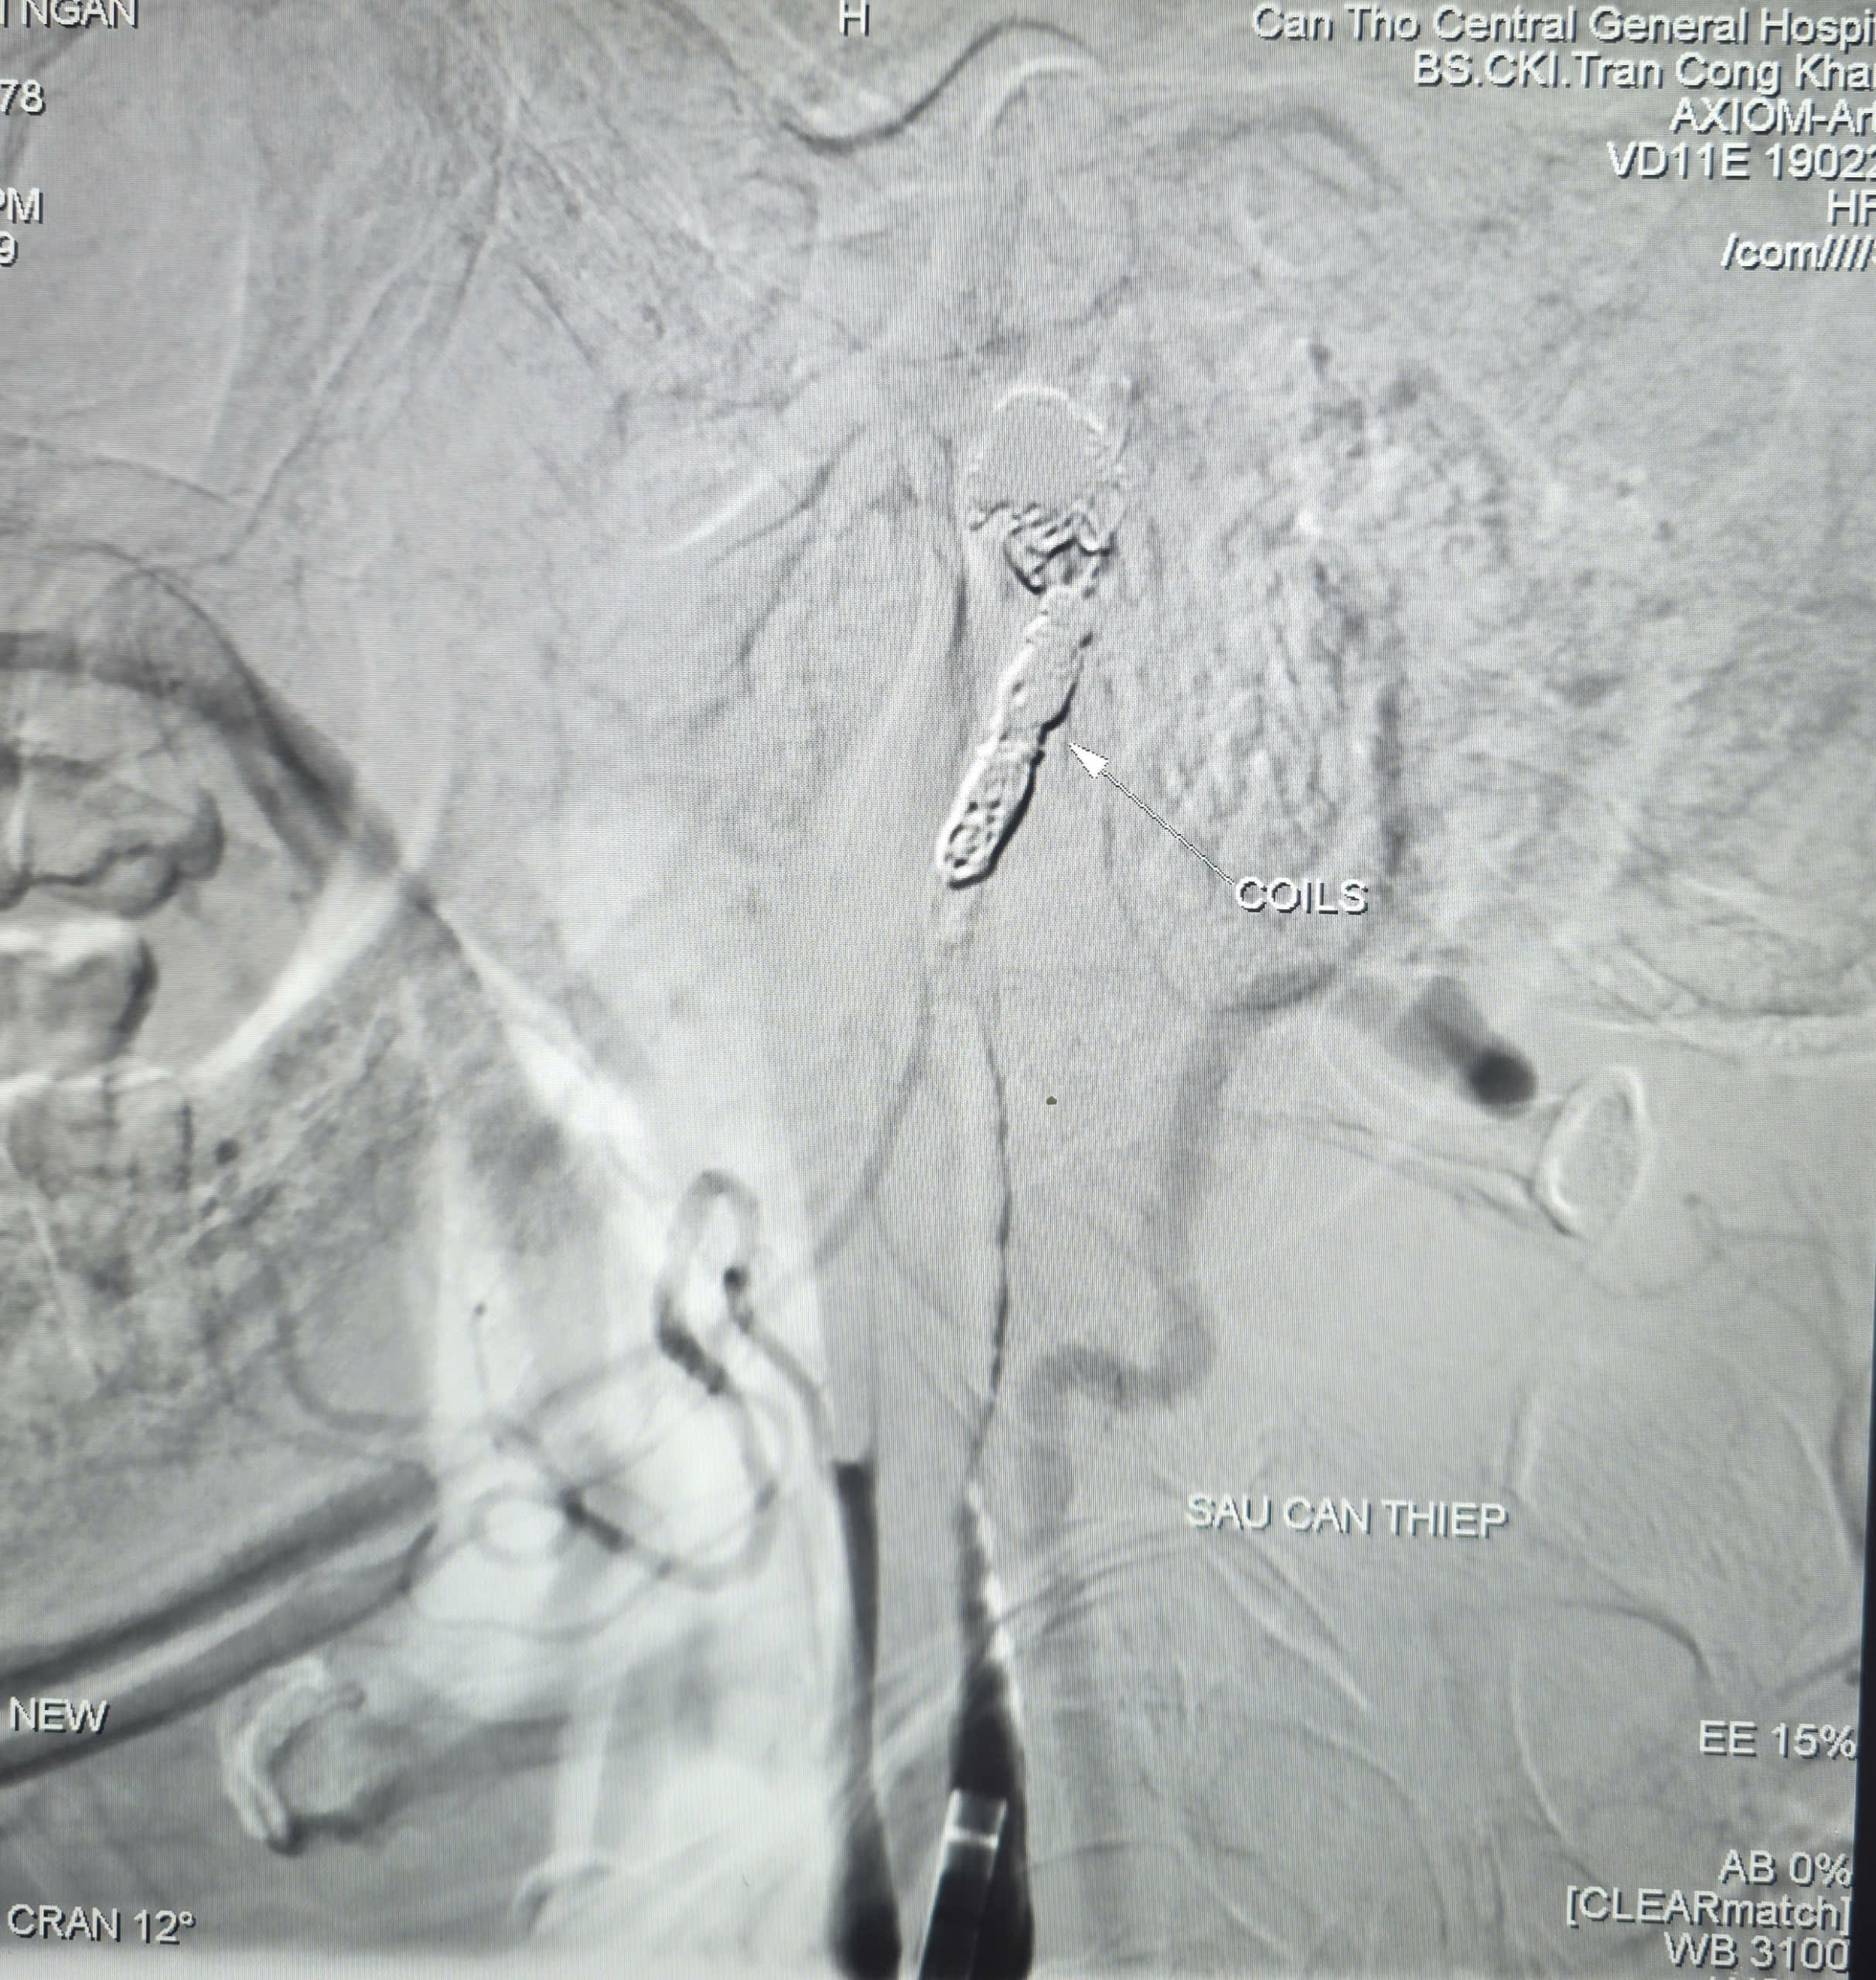

Các bác sĩ quyết định thực hiện chụp và can thiệp cầm máu dưới hệ thống chụp mạch số hóa xóa nền (DSA). Kết quả chụp mạch xác định ổ giả phình động mạch cảnh trong phải đoạn cổ, dưới nền sọ, kích thước khoảng 4,2 x 4,8 mm, cổ túi phình rộng và đang chảy máu.

Các bác sĩ đã dùng bóng chẹn dòng chảy kiểm soát lượng máu, sau đó luồn vi ống thông đến vị trí túi phình và thả 9 vòng xoắn kim loại (coils) để gây tắc hoàn toàn ổ giả phình và động mạch cảnh trong phải, qua đó kiểm soát triệt để nguồn chảy máu. Toàn bộ quá trình can thiệp kéo dài khoảng 90 phút. Đến ngày 6/3, bệnh nhân tỉnh táo, sức khỏe phục hồi khả quan.